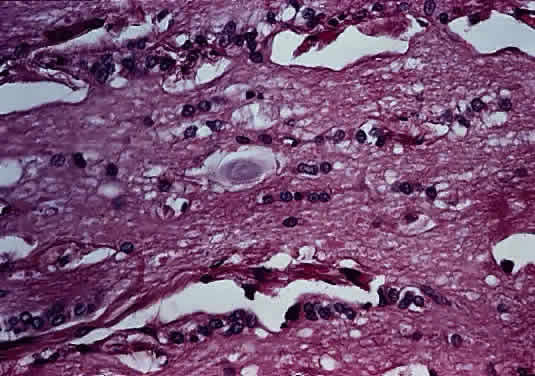

Grossly, optic gliomas that are confined to the orbit appear as fusiform, solid, and somewhat firm expansions of the optic nerve (Fig. 36). They usually blend imperceptibly with the grossly uninvolved nerve at either end. The enveloping dura may be stretched but is not breached. Microscopically, the tumor is composed of bipolar hair-like (pilocytic) astrocytes that infiltrate between preexisting axons and expand rather than compress the nerve fascicles. The neoplastic cells are only mildly atypical, and mitotic figures are typically absent. Not uncommonly, the tumor “spills over” into the subarachnoid space, forming a collar (Fig. 37).

Fig. 37. Pilocytic glioma of optic nerve (hematoxylin and eosin staining). Low power on left shows nerve surrounded by thickened meninges. High power on right shows spindle-shaped cells.

Two histologic features that are present in nearly every example of pilocytic astrocytoma are Rosenthal fibers and eosinophilic granular bodies. Rosenthal fibers are enlarged, brightly eosinophilic cell processes that are sausage or corkscrew-shaped. On Masson trichrome staining, they are bright red (Fig. 38). Ultrastructurally, Rosenthal fibers are defined by amorphous aggregates of electron-dense material within the nerve processes. The number of Rosenthal fibers in different tumors and even within an individual tumor varies considerably; rarely, they are absent entirely. Granular bodies, as the name suggests, consist of rounded eosinophilic proteinaceous structures (Fig. 39). Neither Rosenthal fibers nor granular bodies are unique to pilocytic astrocytomas and are commonly seen in other low-grade astrocytic neoplasms (e.g., ganglioglioma). Their presence, however, essentially excludes a high-grade glioma.